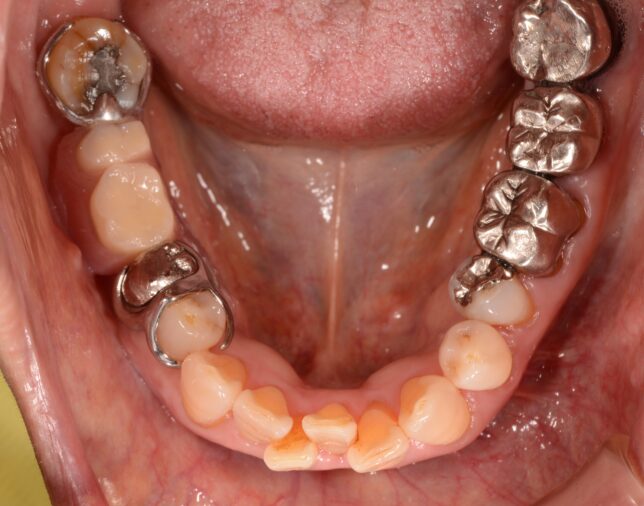

そして、いわゆる通常の入れ歯はこんな感じです。見辛くてスミマセン。拡大してご覧下さい↓

例えば、部分入れ歯(下の画像のような入れ歯)を入れている場合、入れ歯の部分より、入れ歯ではないご自身の歯の方が噛みやすいので、食事の際には無意識に、入れ歯ではない方の歯で噛む回数が増えてしまいます。

たとえば右の歯に部分入れ歯を入れていたら、左の歯でばかりで噛んでしまい、左の健康な歯を過重負担で傷めてしまうということです。